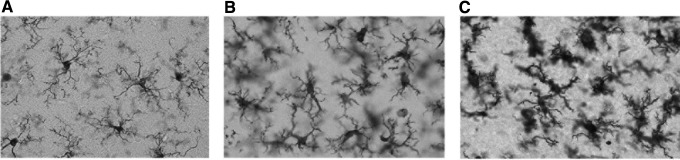

At 24 h after TBI, evidence for different states of microglial activation was demonstrated in the cerebral cortex of mTBI animals compared with sham operated controls. Using anti-Iba1 immunohistochemistry, microglia from sham operated animals displayed surveillant body types with thin and highly branched processes (Fig. 4A). In contrast, cortical specimens from mTBI rats of both temperature groups showed evidence of activation including hypertrophied cell bodies with stubby and swollen short processes (Fig. 4B,C). Also present, especially in the hyperthermic mTBI animals, were cells that were more rounded and also stained with anti-Iba1. These cells were commonly located around blood vessels and appeared to be infiltrating monocytes (data not shown).

FIG. 4.

Iba1 immunohistochemistry demonstrated morphological changes after traumatic brain injury (TBI) in both normothermia (B) and hyperthermia (C) compared with sham animals (A) in the ipsilateral cortex. The morphology of the microglia in sham (A) exhibited a surveillant phenotype, whereas in normothermic TBI animals (B) there was an increase in reactive phenotype and a further activation and ameboid appearance of the microglia in hyperthermic TBI (C) microglia. A, B, C: 60 × magnification.

We next assessed whether significant differences in the degree of microglial activation could be demonstrated between the two mTBI temperature groups. Using non-biased stereological approaches, Iba1 immunoreactive microglia were characterized in the ipsilateral cerebral cortex and placed in one of three categories including surveillant, activated, and ameboid.65,66 Numbers of surveillant, non-activated cells decreased significantly in normothermic (#p < 0.05) and hyperthermic (*p < 0.001) groups compared with sham (Fig. 5A). Counts of reactive and ameboid microglia were significantly increased in mTBI rats compared with sham operated animals (Fig. 5B,C; #p < 0.05). In addition, numbers of reactive and ameboid microglia were significantly increased in the hyperthermic versus normothermic mTBI animals (Fig. 5 B,C; **p < 0.05). These immunohistochemical findings demonstrate that hyperthermic mTBI augments the microglial response to trauma compared with normothermic conditions.